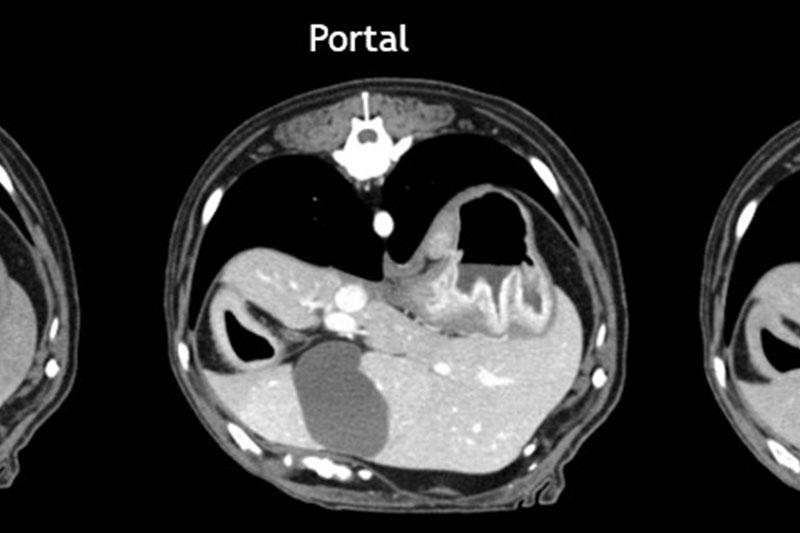

| 복부 | 간, 비장, 신장, 위장관 종양 및 결석, 부신, 림프절 등 |

혈관 조영(Angio CT)을 통한 혈관 이상 진단